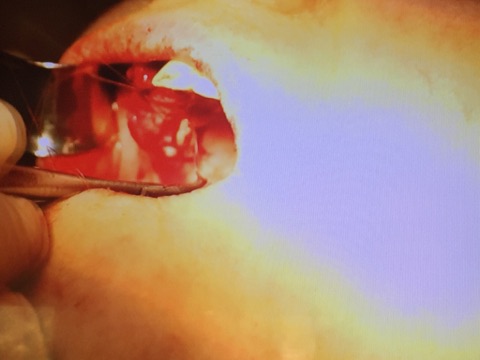

Мастер-класс начался с обсуждения предстоящей операции и снимка компьютерной томографии, после чего участники смогли присутствовать на операции.